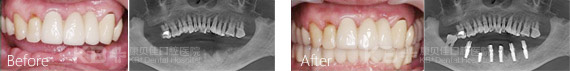

种植牙后依旧抽烟,导致种植牙宣告失败

今年68岁的刘大爷在子女的陪同下来康贝佳做了种植牙修复手术,不料没过多久刘大爷居然发现种植牙有些松动,为此刘大爷急忙复诊。负责种植牙手术的慕林林主任为刘大爷做了详细的口腔检查,检查发现种植牙之所以出现松动现象,主要是因为口腔卫生没有做好导致的。

经过详细的交流刘大爷才说出了实情,原来种完牙后,医生叮嘱刘大爷一定不能抽烟,可是刘大爷烟瘾犯了,瞒着家人隔三差五悄悄抽烟。正是由于刘大爷不听医生的劝告和叮嘱,导致刘大爷的种植牙以失败告终,只能重新进行返工修复。

慕主任再次强调种植牙是牙齿修复较好的方法,但后期维护很重要。有研究显示,吸烟者的愈合能力只能是非吸烟者的28%,使种植效果大打折扣。此外,抽烟使口腔温度升高,局部出现厌氧环境,让细菌有机可趁,容易造成种植牙的松动和脱落。建议至少初次在手术前一周以及术后8周期间是一定不能抽烟的。

除此之外,烟草中含有4000多种有毒成分。这些成分中特别是尼古丁会使末梢血管收缩,影响血液循环,组织伤口愈合,影响种植体跟骨的结合。还会引发免疫细胞机能低下,降低骨密度,所以会显著降低种植体的使用寿命。